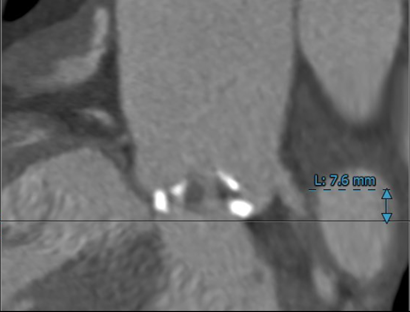

左冠开口高度较低,仅7.6mm,有冠脉堵塞风险;右冠开口15mm,无明显冠脉堵塞风险。